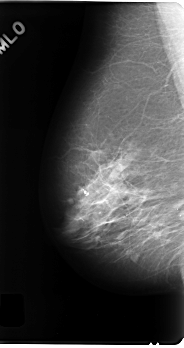

C_0177_1.RIGHT_MLO

RIGHT_MLO LINES 4872 PIXELS_PER_LINE 2568 BITS_PER_PIXEL 12 RESOLUTION 50 NON_OVERLAY